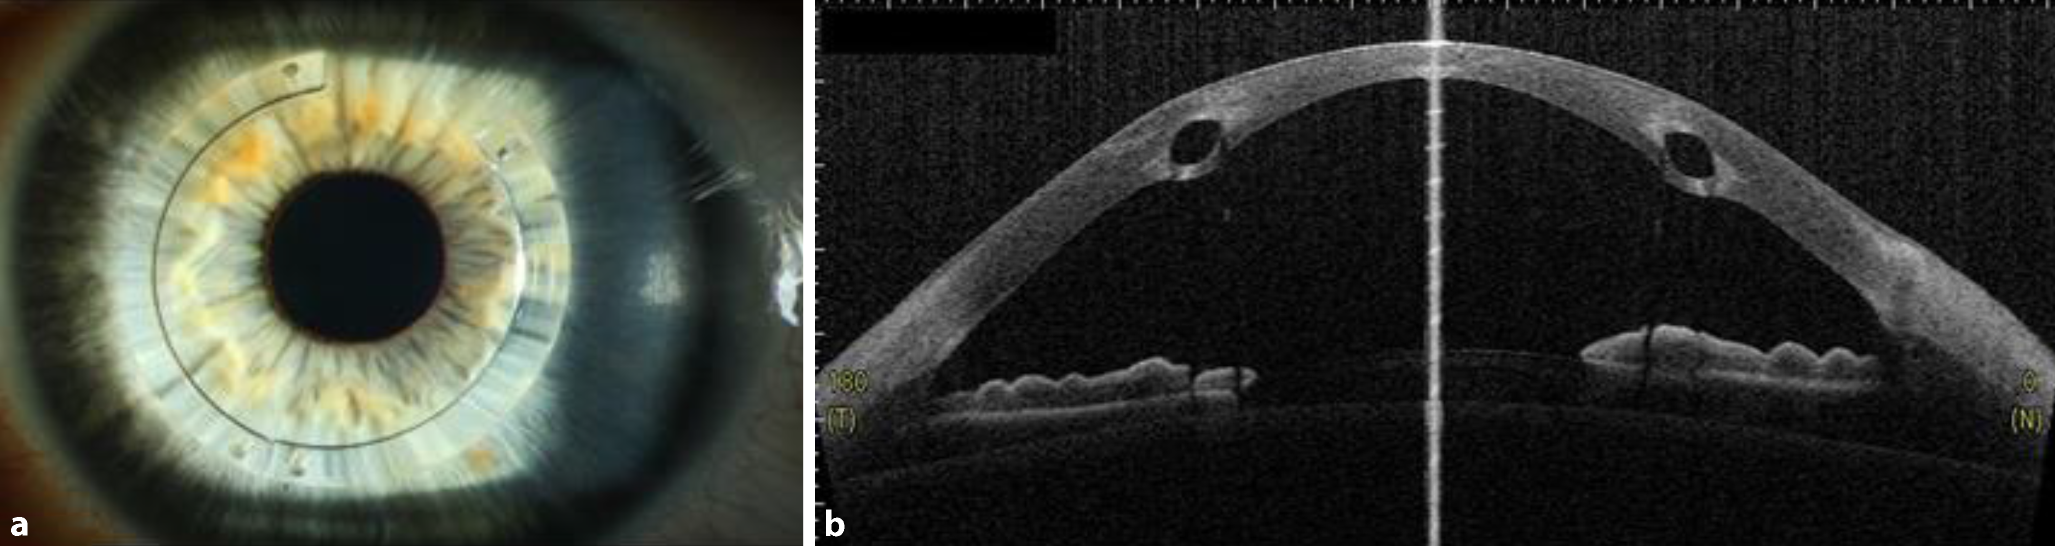

Die intrastromalen Hornhautimplantate stellen eine elegante und effektive Option dar, um den unkorrigierten und bestkorrigierten Visus zu verbessern und (wie durch ein „Korsett“) auch die Progression des Keratokonus einzudämmen (Abb. 9a, b). In einer Langzeitstudie mit einem Follow-up von im Mittel 3 Jahren zeigten nur 2,7 % der Patienten unter 35 Jahre eine Progredienz des KK nach reiner INTACS-Implantation [57]. Nichtsdestoweniger ist prinzipiell eine Kombinationstherapie mit CXL möglich – besonders bei jüngeren Patienten mit stärkerer Progressionstendenz. Vor allem Patienten mit einer Intoleranz gegenüber formstabilen Kontaktlinsen profitieren von dem abflachenden – also hyperopisierenden – Effekt der intrastromalen Hornhautimplantate, sodass oftmals bei „regularisiertem Astigmatismus“ wieder eine Brillen- oder Kontaktlinsenanpassung möglich wird.

Abb. 9

Intrastromale Hornhautimplantate stellen eine elegante und effektive Option dar, um bei mäßiggradigem Keratokonus die Hornhautverkrümmung abzuflachen und zu regularisieren und so den unkorrigierten und bestkorrigierten Visus zu verbessern. a Spaltlampenübersicht. b Die beiden ovalären Polymethylmethacrylat(PMMA)-Ringsegmente liegen symmetrisch in 80 % Tiefe der Hornhaut (VA[Vorderabschnitt]-OCT [optische Kohärenztomographie])

Voraussetzung für die Implantation von ICRS sind eine Hornhautdicke von > 450 µm in der 6‑ bis 7‑mm-Implantationszone der Vorderabschnitts-OCT und eine narbenfreie optische Zone. Die zentrale Hornhautdicke spielt hierbei eher eine untergeordnete Rolle. Die Lage, Dicke und Geometrie der Halbringe wird individuell entsprechend dem Nomogramm der Herstellerfirma angepasst.